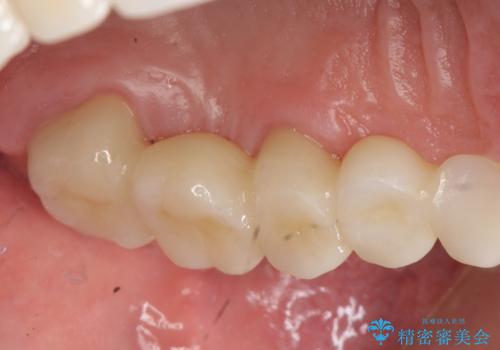

インプラントは希望されなかったため、左側は1番から7番のロングスパンブリッジによる補綴を行いました。

オールセラミッククラウンについて

今回用いたオールセラミッククラウンは、ジルコニアフレームという白い素材の上にセラミックを盛っているため審美性が非常に高いのが特徴です。

またジルコニアは人工ダイヤモンドの材料にも使われているほど高い強度を持っており、そのためオールセラミッククラウンは審美性だけでなく、奥歯やブリッジの補綴も可能とするクラウンです。